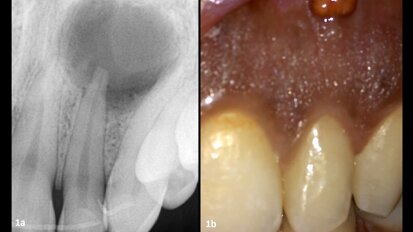

The male patient was a former smoker and 51 years old when the treatment was initiated. He presented with high blood pressure and took Tahor (Pfizer) on a daily basis. In addition, he had been on Kardegic (Sanofi) therapy since a heart attack in 2005. For functional and aesthetic reasons, he wanted a fixed prosthesis in his maxillary arch (Figs. 1a & b).

embedImagecenter("Imagecenter_1_1419",1419, "large");